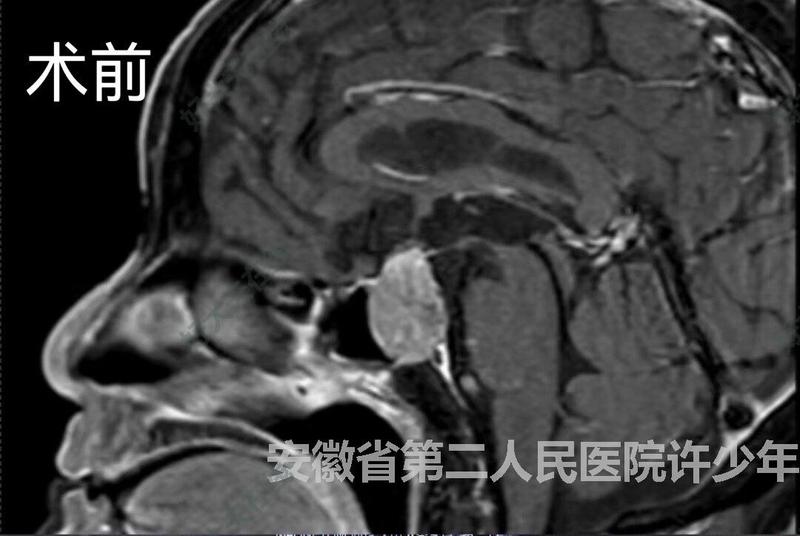

神經(jīng)內(nèi)鏡

治療前大年三十視力下降,頭痛惡心嘔吐,左眼瞼下垂,由安徽省第二人民醫(yī)院靈璧醫(yī)院急診轉(zhuǎn)至我科,急診完善術(shù)前準(zhǔn)備后,神經(jīng)內(nèi)鏡下經(jīng)鼻入路行垂體瘤切除術(shù)。治療中術(shù)中證實(shí)腫瘤卒中,侵襲左側(cè)海綿竇,完整切除腫瘤,鞍隔塌陷,無(wú)腦脊液滲漏治療后治療后即刻術(shù)后目前視力視野基本正常,小便正常,激素水平均正常,眼瞼無(wú)下垂,今天新年假期最后一天出院回家。

許少年醫(yī)生的科普號(hào)2024年09月29日36